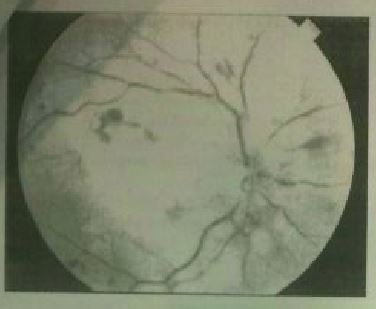

Question 20

Question

Esta imagen corresponde a:

Answer

• a. DMAE

• b. Retinopatía diabética proliferante

• c. Desprendimiento de Retina tratado mediante aceite de silicona

• d. Oclusión de la arteria central de la retina